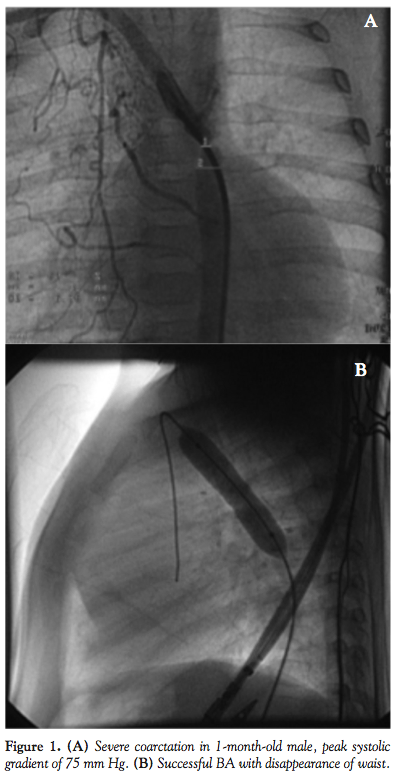

Catheterization and angioplasty data. The peak-to-peak systolic pressure gradient across the coarctation site was measured before and after angioplasty procedures. The diameters of the coarctation site were recorded. Most measurements were obtained from the systolic frames and lateral projections (Figure 1).